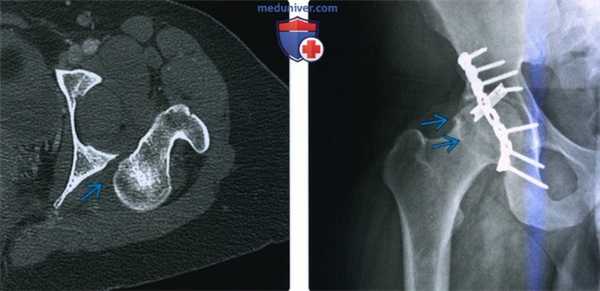

(Слева) КТ, аксиальный срез: в данном вывихе, репозиция которого возможна только под общей анестезией, визуализируется головка бедренной кости, вколоченная в заднюю губу вертлужной впадины.

(Справа) Рентгенография в передне-задней проекции: у пациента 25 лет, спустя год после заднего вывиха бедра, определяется остеофит, указывающий на ранний остеоартрит. Несмотря на то, что бедро было немедленно подвергнуто репозиции и фиксация перелома задней стенки была полностью анатомически правильная (с помощью длинной реконструктивной пластины и короткой трубчатой пластиной 1/3 длины), повреждение нижележащего хряща быстро привело к остеоартриту.